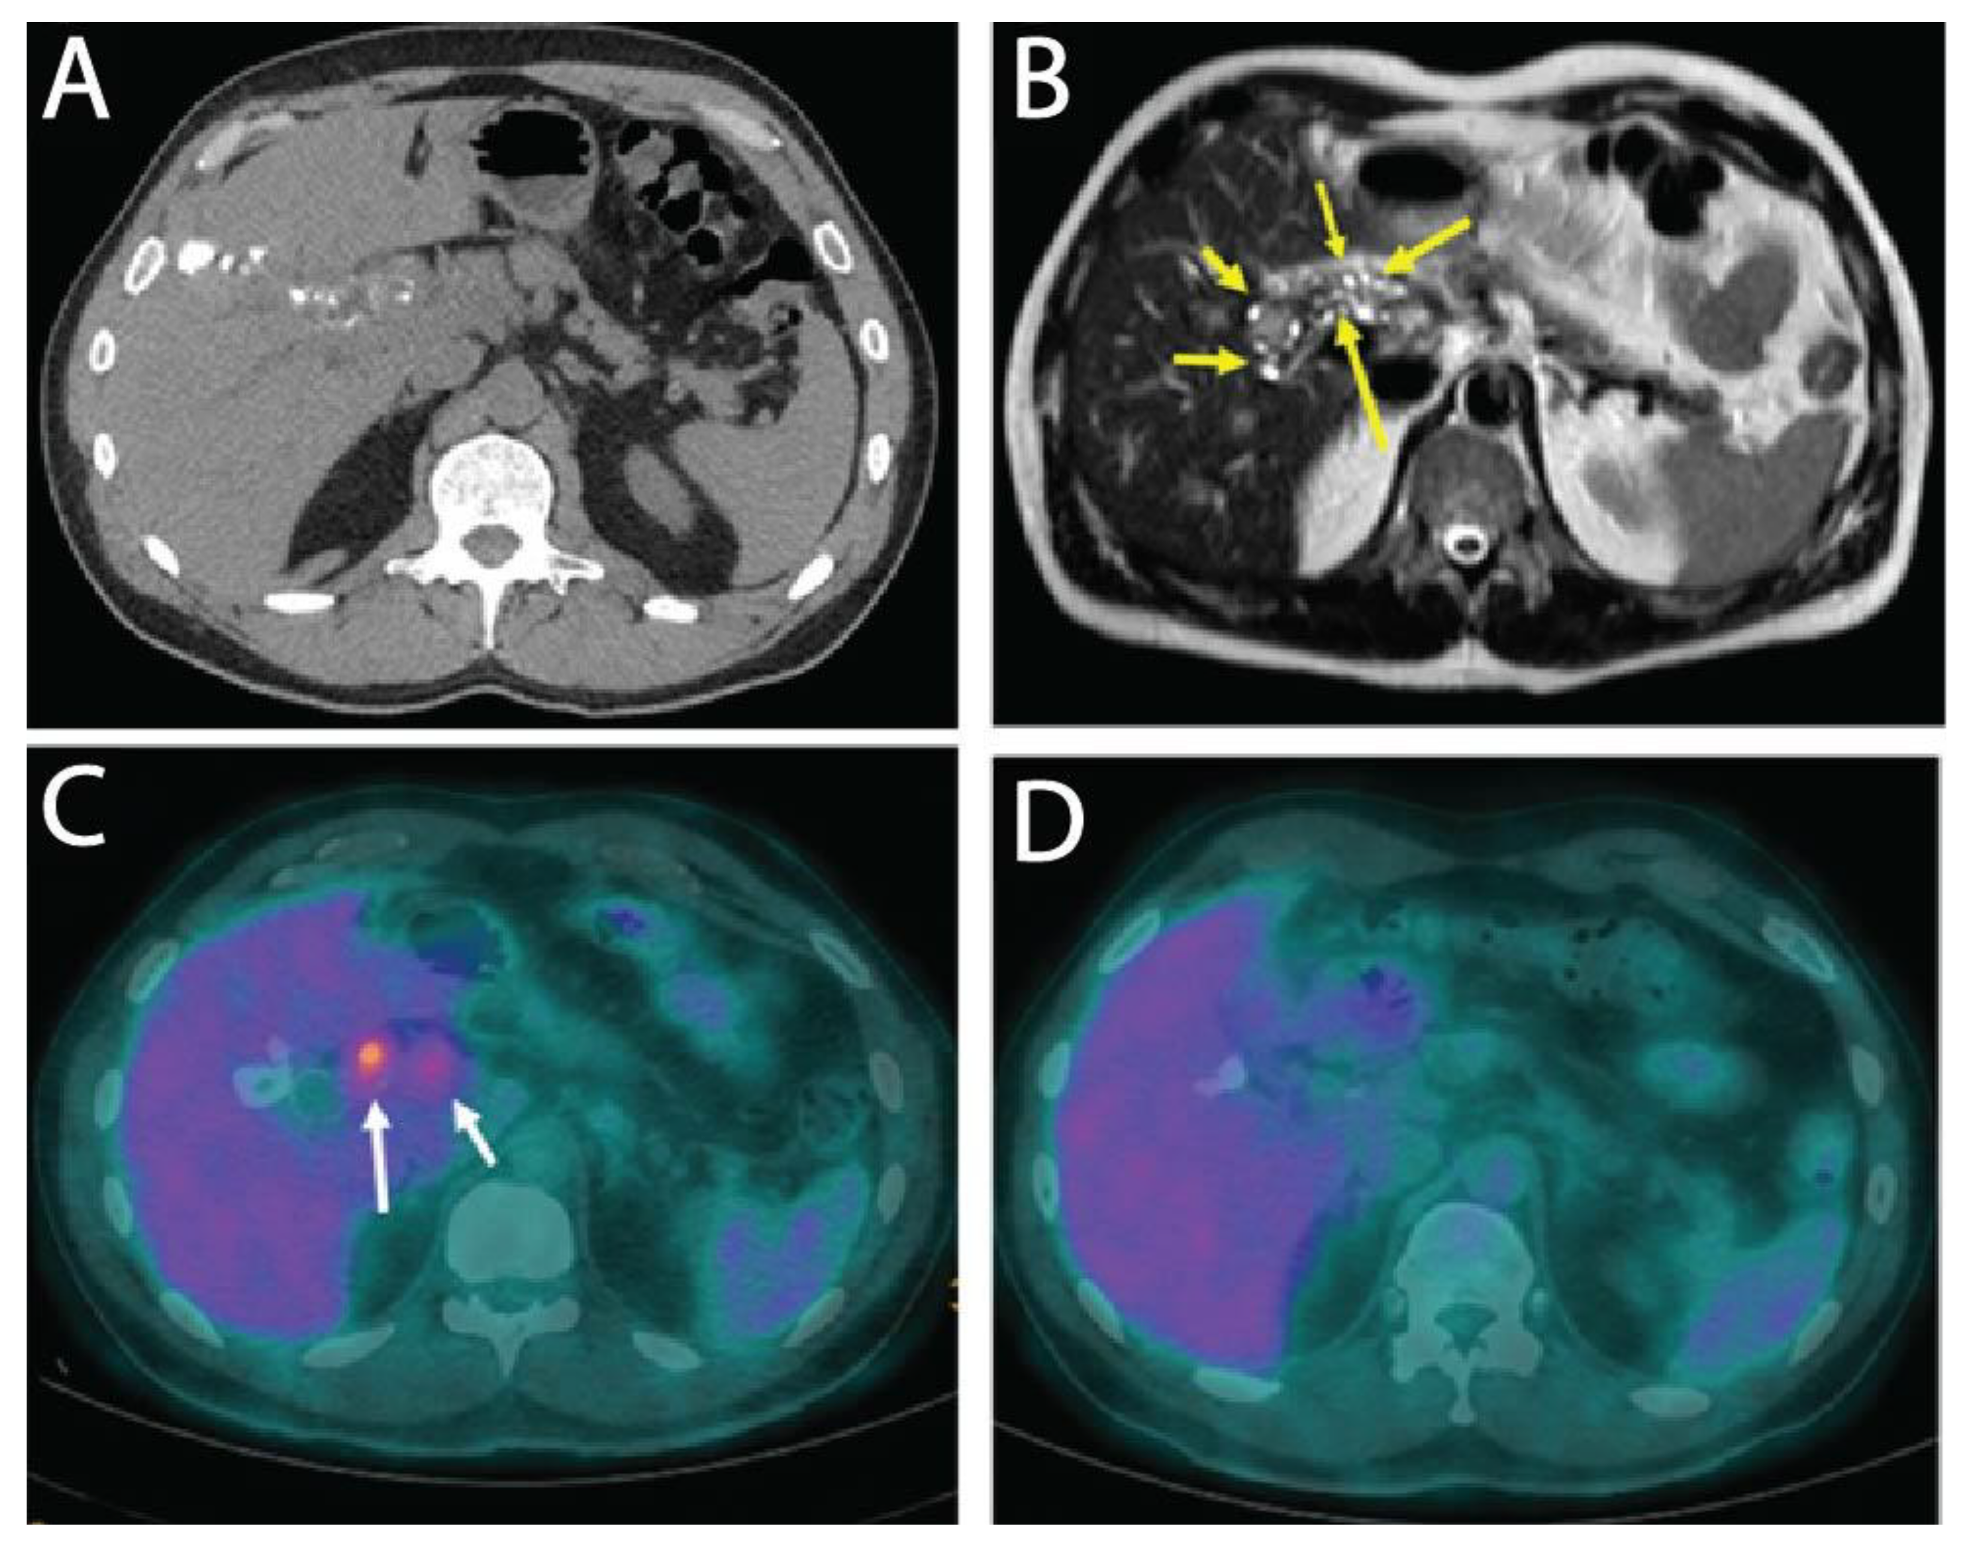

Here, we report on a clinical case of AE, where the involvement of a medicinal plant extract has been implicated. In mid-July 2013, a 56-year-old man working as executive in industry and living near Paris without any history of significant health issues presented an isolated jaundice associated with fatigue. Abdominal ultrasonography and computed tomography (CT) indicated an aberrant liver mass located in the hilar region associated with intra-hepatic bile ducts dilatation (Figure 1A). A cholangiocarcinoma was suspected and the patient was referred to the hepato-biliary reference center at Paul Brousse Hospital (France). At admission a liver and cholangio-magnetic resonance imaging (-MRI) was performed. It confirmed the presence of a perihilar infiltrative tissular mass. However, hyper-T2 sequences showed multiple microcystic structures within the lesion (Figure 1B and Figure 2A). This aspect, associated with many other lesions in the right liver (segment V and VIII) with mixed composition (cystic and calcified areas) when rereading the CT images, raised suspicion of AE. Specific serology confirmed this diagnosis (with 26–28 kDa and 16 and 18 kDa positivity on Western Blot for confirmation. Thus, continuous ABZ therapy was introduced (400 mg bid). The patient had travelled a lot for professional reasons, mainly in Asia and South America but not in areas that are endemic for AE. However, before moving to Paris, he was living in Eastern France from 2001–2007, in a village located in Lorraine, an area known to be endemic for AE [16]. There, he had an open vegetable garden, which was frequently accessed by foxes that also came very close to the patient’s house. The patient did not own dogs or cats. A first PET-CT in August 2013 showed strong hypermetabolic perilesional foci surrounding the hilar lesion (Figure 1C); another hypermetabolic focus was described along the choledochus until the cephalic pancreas. There was no perilesional activity in the right liver but this first PET-CT did not include the late acquisitions images (+ 3 h) that are recommended for AE lesions evaluation [17]. Moreover, a more extended lesion check-up was performed: a thoracic CT-scan and cerebral MRI did not reveal AE metastases. The PNM stage (8) was P4N0M0, stage IIIb.

Subsequently, the situation evolved favorably without any new clinical event. In September 2013 jaundice disappeared. Biological follow-up indicated a stable normalization of liver enzymes during the 6-year follow-up. ABZ was very well tolerated with excellent observance and optimal pharmacological results (concentrations always maintained between 2 and 4 µmol/L with no posology adaptation due to good tolerance). In April 2014, the biliary stent was replaced by three juxtaposed plastic stents allowing calibration of the main stenosis located on the left biliary duct. Regular stent replacements were performed every 3 to 6 months until May 2015, then stents were definitively removed. The clinical, biological course remained uneventful, and the patient returned to completely normal activities. Furthermore, the specific serological follow-up for AE was extremely favorable, as it showed a continuous decrease in Em2+ ELISA index (from 1.27 initially to negativity at 0.49 and 0.44 in September 2018 and 2019, respectively) and anti-Em18 reactivity also disappeared. Very interestingly and totally unexpectedly, so close to the diagnosis and initiation of ABZ, MRI follow-up indicated a complete disappearance of hyper-T2 microcysts at 42 months post ABZ initiation (Figure 2B). PET-CT sequential evaluation with 1 and 3 h acquisition following a specific protocol for AE [17] indicated a regular decrease in perilesional activity to complete negativation during 2015–2018 (Figure 1D). This was confirmed in 2019. The patient had a strong demand to discontinue ABZ treatment. After a multidisciplinary meeting at the Besançon Reference Center, the decision for ABZ interruption after an 80 month duration was validated in March 2020 under strict follow-up. The first evaluation at 6 months post-treatment interruption, in September 2020, indicated negative specific serological results, normal liver values, and the patient’s physical condition remained excellent. The situation remained unchanged in September 2021, with AE serology negative, normal liver enzymes, and total bilirubinemia.

Figure 1. Radiological images of human AE liver. (A) CT image of human AE patient in July 2013, at time of diagnosis showing an infiltrative lesion with scattered calcifications in the right lobe of the liver and extending to the hilum; (B) T2 weighted MR image showing several hyper-T2 microcysts in the perihilar area (arrows) testifying to an active AE lesion; (C) FDG-PET at time of diagnosis, early acquisition image (1 h after FDG injection): obvious FDG uptake around the perihilar parasitic mass (arrows); (D) FDG-PET in 2018, under ABZ therapy for 54 months, late acquisition image (3 h after FDG injection): no perilesional activity.